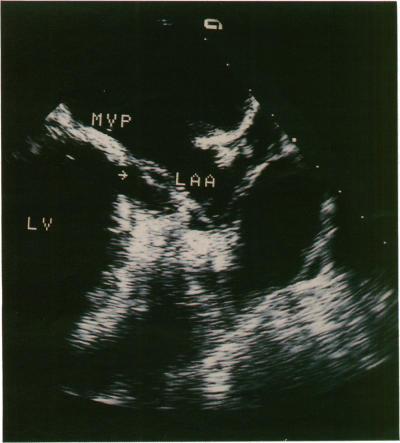

To determine whether biplane transoesophageal imaging offers advantages in the evaluation of mitral prostheses when compared with standard single transverse plane imaging or the precordial approach in suspected prosthetic dysfunction.

Transverse plane transoesophageal imaging alone identified all 31 medial/lateral paravalvar leaks but only 24/30 of the anterior/posterior leaks. Combining the information from both imaging planes confirmed that biplane scanning identified all paravalvar leaks. Five of the six patients with prosthetic valve endocarditis, all three with valvar thrombus or obstruction, and all three with mitral annulus rupture were diagnosed from transverse plane imaging alone. Longitudinal plane imaging alone enabled diagnosis of the remaining case of prosthetic endocarditis and a further case of subvalvar pannus formation.

Transverse plane transoesophageal imaging was superior to the longitudinal imaging in identifying medial and lateral lesions around the sewing ring of a mitral valve prosthesis. Longitudinal plane imaging was superior in identifying anterior and posterior lesions. Biplane imaging is therefore an important development in the study of mitral prosthesis function.